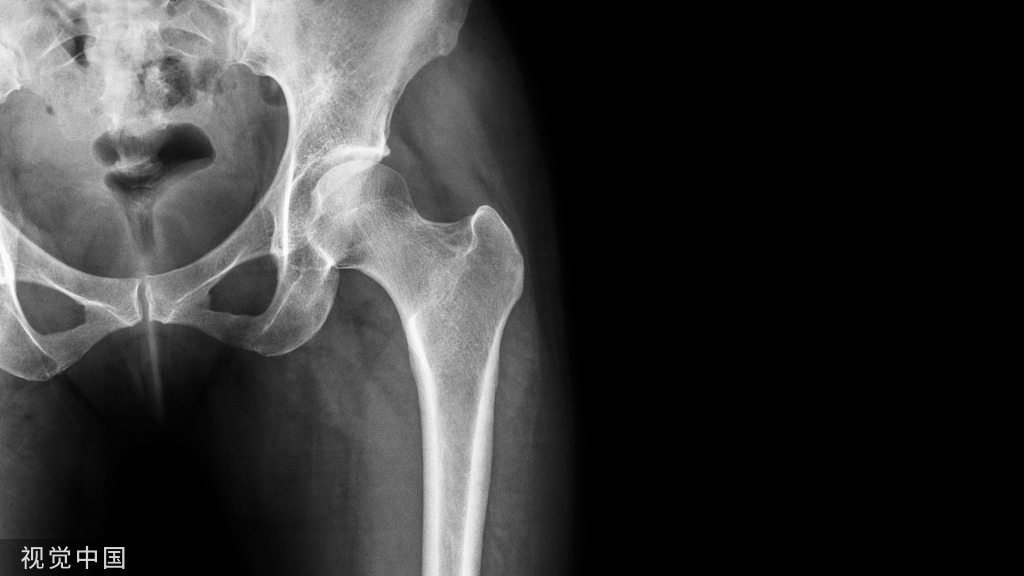

诊断:前列腺癌、骨转移。

5、高BMD、ALP高可能为前列腺癌、畸形性骨炎、骨纤维异样增殖症等疾病;